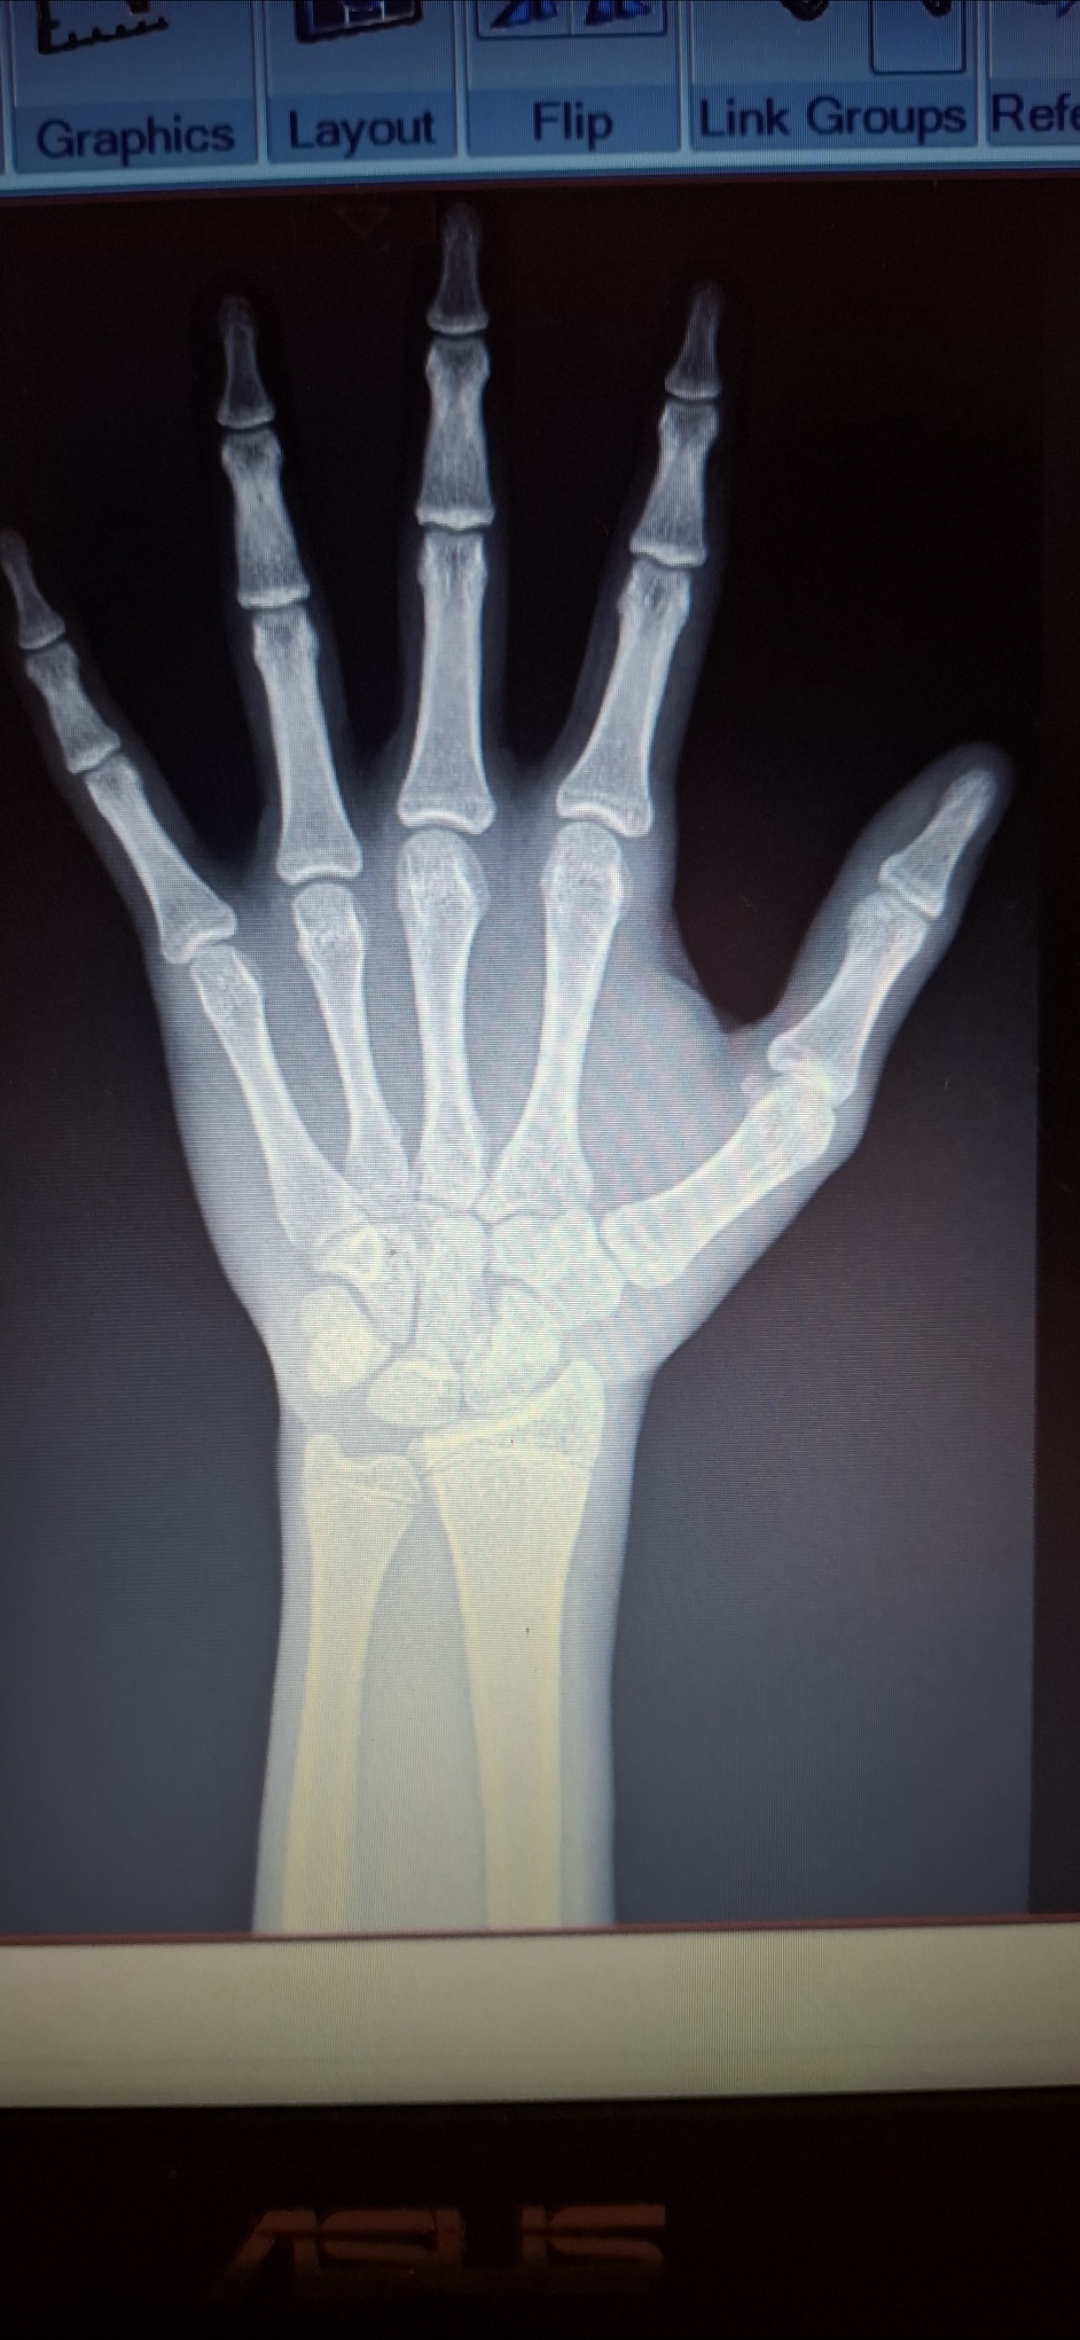

Doesnt look to be fully closed but you definitely need to get on an ai cuz their closeView attachment 4415572 I grew an inch past 3 months but on the scan they look closed

theres clearly cartilage in the radius and ulna, I will admit the growth plates in his hands look fused but those are commonly the first to fuse anywaysSeems closed![]()